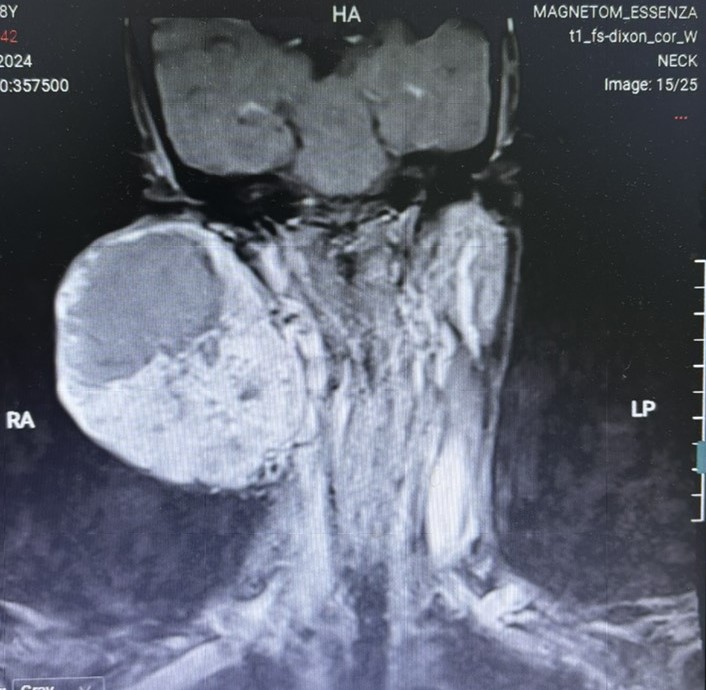

Các bệnh ung thư khácSự kiện, Hoạt độngTrì hoãn 14 năm không điều trị, Người phụ nữ suýt mất mạng vì khối U " Khổng lồ" trên mặt Chi tiết